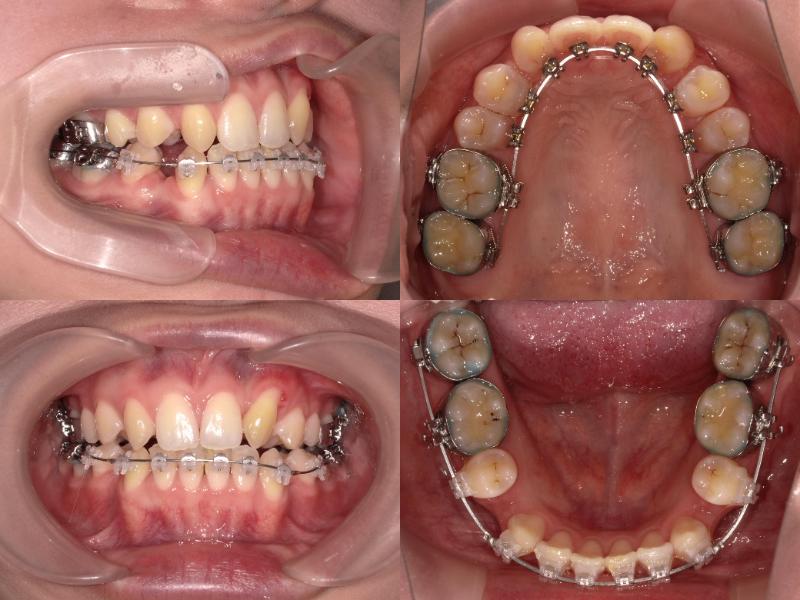

上下顎前突、過蓋咬合および左上7番の根尖性歯周炎の治療

上下左右5番を抜歯し、上顎6番を口蓋正中縫合部からアンカースクリューで固定。

さらに、上顎2・3番の間に埋入したアンカースクリューから前歯を圧下し、口元の突出感とディープバイトの改善を図りました。

初診時年齢25歳1ヵ月の患者様です。

口元の突出感を主訴にご来院されました。

過蓋咬合と左上7番の根尖性歯周炎が認められたため、通常であれば上下左右4番を抜歯しますが、上下左右5番が処置歯であったため、5番を抜歯しました。

上顎6番を口蓋正中縫合部からアンカースクリューで固定し、さらに上顎2・3間に埋入したアンカースクリューから前歯を圧下しました。